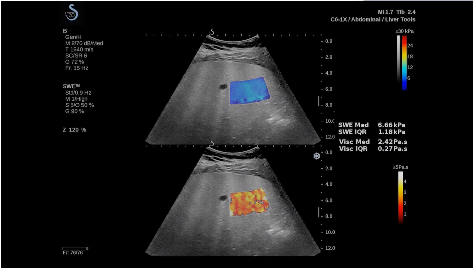

法國聲科影像(SuperSonic Imagine,SSI. Euroniex:FR0010526814)近日發(fā)表公告,宣布其研發(fā)的新一代“極速”超聲成像平臺(UltraFast Imaging),首次實現(xiàn)了肝臟的多項超聲定量評估新指標同步檢測,包括:Att PLUS,SSp PLUS和Vi PLUS等,基本涵蓋肝臟相關(guān)病理變化指征的如纖維化、脂肪變、炎癥等。據(jù)悉,此多項新技術(shù)新將搭載于新Aixplorer系列E超系統(tǒng)。

法國聲科影像公司(SuperSonic Imagine. SA,F(xiàn)rance),2005年由三位諾貝爾獎級科學家主導(dǎo)創(chuàng)立,專注于E超的開發(fā)和生產(chǎn),是目前世界上唯一可以同時應(yīng)用兩種波進行人體檢測的系統(tǒng):縱波形成高質(zhì)量的二維組織結(jié)構(gòu)圖像,而橫波可以使醫(yī)生實時準確地看到并分析組織的硬度,有效減少有創(chuàng)檢查、避免損傷。

E超相關(guān)技術(shù)已被多項多中心大樣本研究證實對于肝纖維化無創(chuàng)評估有重要意義,同時也可全面應(yīng)用于乳腺、甲狀腺、肝臟、前列腺、肌骨、婦科等全身各組織器官的定量評估和鑒別診斷。在慢性肝臟方面,聲科E超的肝臟相關(guān)定量診斷技術(shù)集,于2018年獲得美國FDA認證,成為FDA歷史上首次獲批的單病種超聲全面定量解決方案。

E超是在原有B超、彩超(彩色多普勒CDFI)基礎(chǔ)上研發(fā)成功的新一代超聲剪切波彈性成像系統(tǒng),是一種能夠全面應(yīng)用于表淺組織、腹部臟器,血管等方面的組織彈性成像技術(shù)。根據(jù)組織硬度彈性值的不同,有效鑒別實性腫瘤的良惡性。對于惡性病變的診斷具有較高的特異性和敏感性,尤其對于甲狀腺、乳腺、前列腺等小器官,能夠完成常規(guī)超聲不能完成的組織定量分析,可以實時、全幅、全定量獲得組織彈性(硬度)信息,為鑒別腫瘤的良惡性提供客觀、量化的診斷依據(jù)。